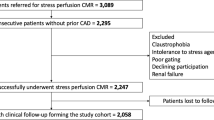

Of the 35,280 patients referred for stress CMR during the inclusion period, 1584 (4.5%) patients were referred for dipyridamole vasodilator stress CMR because of a first inconclusive noninvasive stress test. Among those, 1563 (98.7%) completed the stress protocol, as detailed in the flowchart (Fig. 1). Of the 1563 patients who successfully underwent stress CMR, the diagnosis of ischemia was inconclusive in 24 patients (1.5%) due to nondiagnostic image quality, arrythmias or artifacts. Out of these 1563 patients, 61 failed to respond to dipyridamole injection as assessed by the rate-pressure product (3.9%). No patient died during or shortly after CMR, and detailed safety results are presented in Additional file 5. Overall, 1402 patients completed the clinical follow-up and constituted our study cohort. Baseline subject characteristics and baseline CMR data are shown in Table 1. Among those 1402 patients (66.7% male, 69.5 ± 11.0 years), 58.4% had dyslipidemia, 57.6% had hypertension, 32.7% had diabetes mellitus, 30.7% had obesity, 27.9% had a family history of CAD and 24.0% were smokers. Overall, 727 (51.9%) patients had known CAD. Of note, 247 (17.6%) of patients were in atrial fibrillation or supraventricular arrhythmia. Regarding the first inconclusive stress test, 702 (50.1%) patients had a prior inconclusive stress echocardiography, 612 (43.7%) a prior inconclusive SPECT (147 dipyridamole SPECT) and 88 (6.3%) a prior inconclusive exercise ECG testing. The two main reasons for an inconclusive stress test were poor image quality (68%) and sub-maximal exercise (29%).